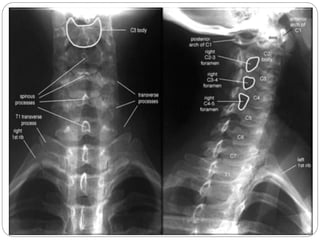

Vértebra Torácica

O processo espinhoso não é bifurcado e se apresenta descendente e pontiagudo.

As vértebras torácicas se articulam com as costelas, sendo que as superfícies articulares dessas vértebras são chamadas fóveas.

O corpo, o pedículo e a lâmina limitam o forame vertebral, que contém a medula espinal.

Vértebra Torácica Oprocesso espinhoso não é bifurcado e se apresenta descendente e pontiagudo. As vértebras torácicas se articulam com as costelas, sendo que as superfícies articulares dessas vértebras são chamadas fóveas. O corpo, o pedículo e a lâmina limitam o forame vertebral, que contém a medula espinal.